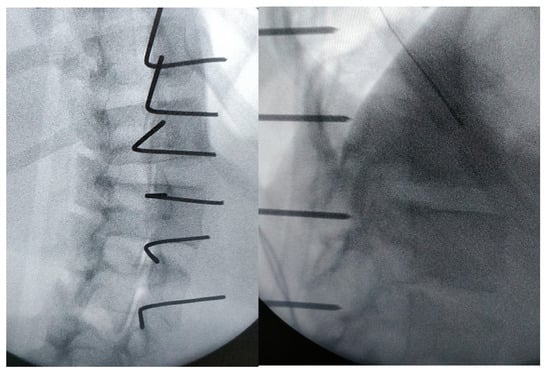

2.2. Surgical Technique